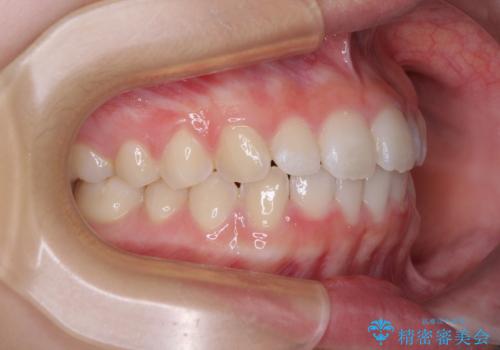

- 前歯のデコボコを気にして来院された高校生の患者様です。

捻れた前歯が前方に飛び出している点も気になっており、目立たない装置を希望されたため、インビザラインを用いて矯正治療を行うこととしました。

上下ともに少し捻れが残っていたため、治療の継続を提案しましたが、本人も親御さんも満足とのことで、治療を終えました。

捻れの改善により突出感も改善されました。